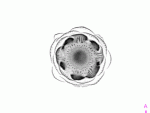

Task: Can you guess what plant you see on the images? Sort the pictures by the order of the MRI section. Draw a 3D image of the original plant!

1. I show the gif on the projector : guess the fruit – write down the answer!

2. Sort the pictures by the order of the MRI section! Glue it on the paper!

Guess what this is?

Yep, an artichoke :)